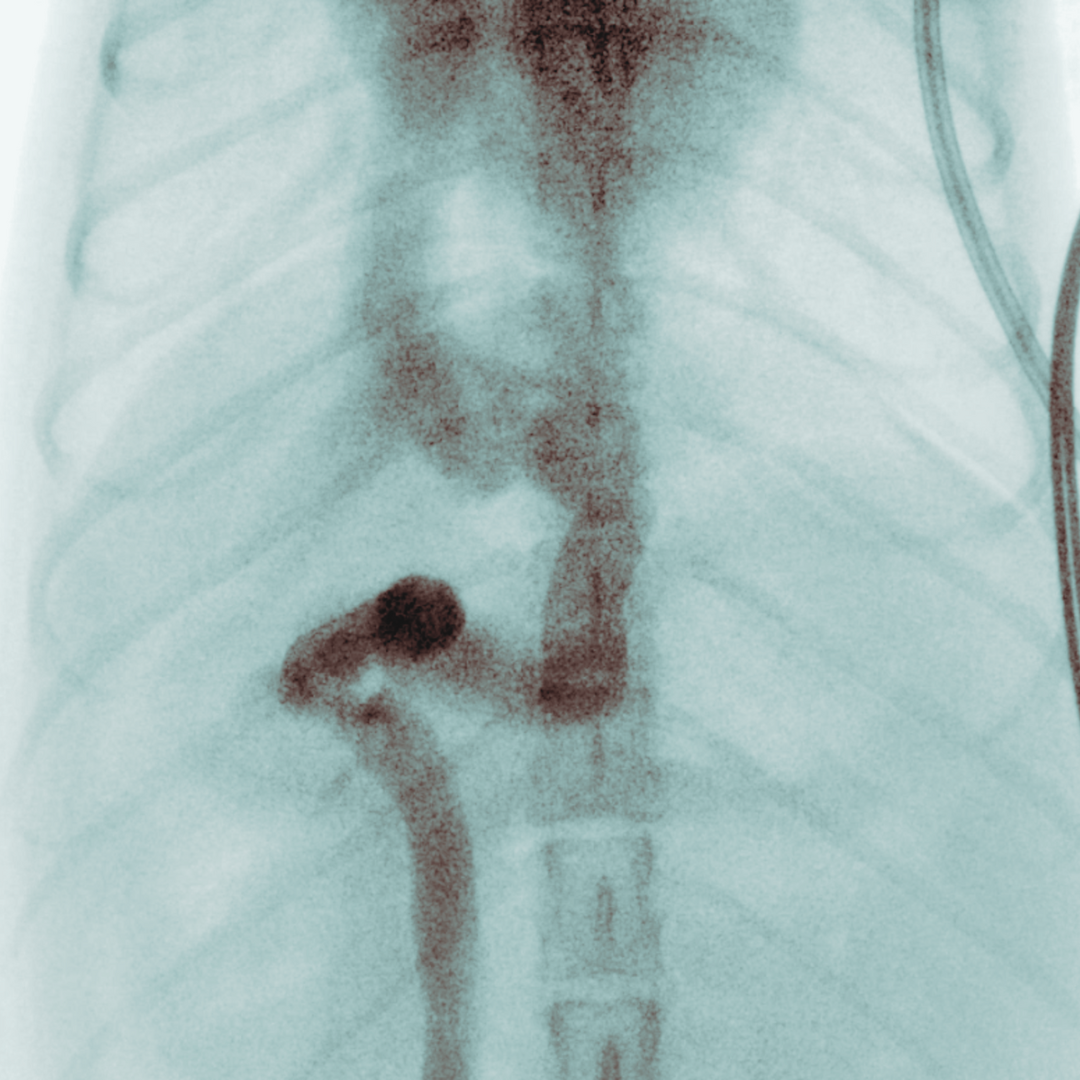

• PSS (portosystemiska shuntar)

– extrahepatisk och intrahepatisk